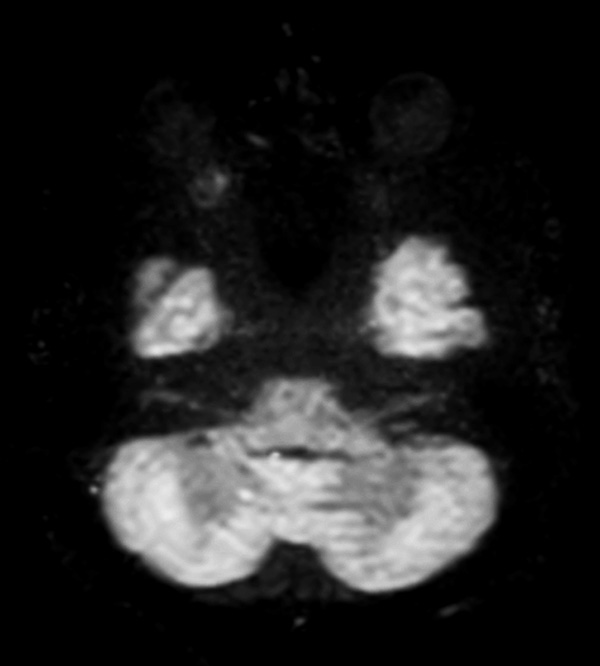

Comprehensive Brain imaging at 1.5T

Used Solution

• Clinical Application